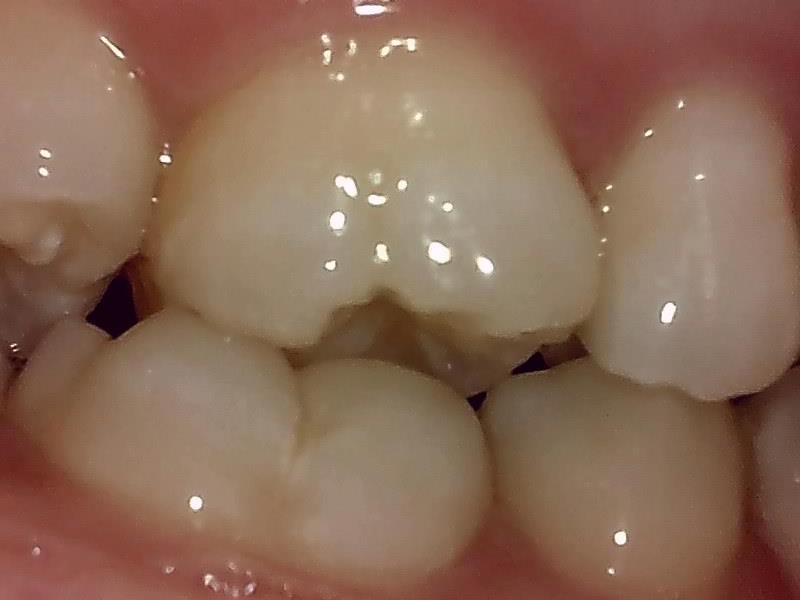

右側

上顎